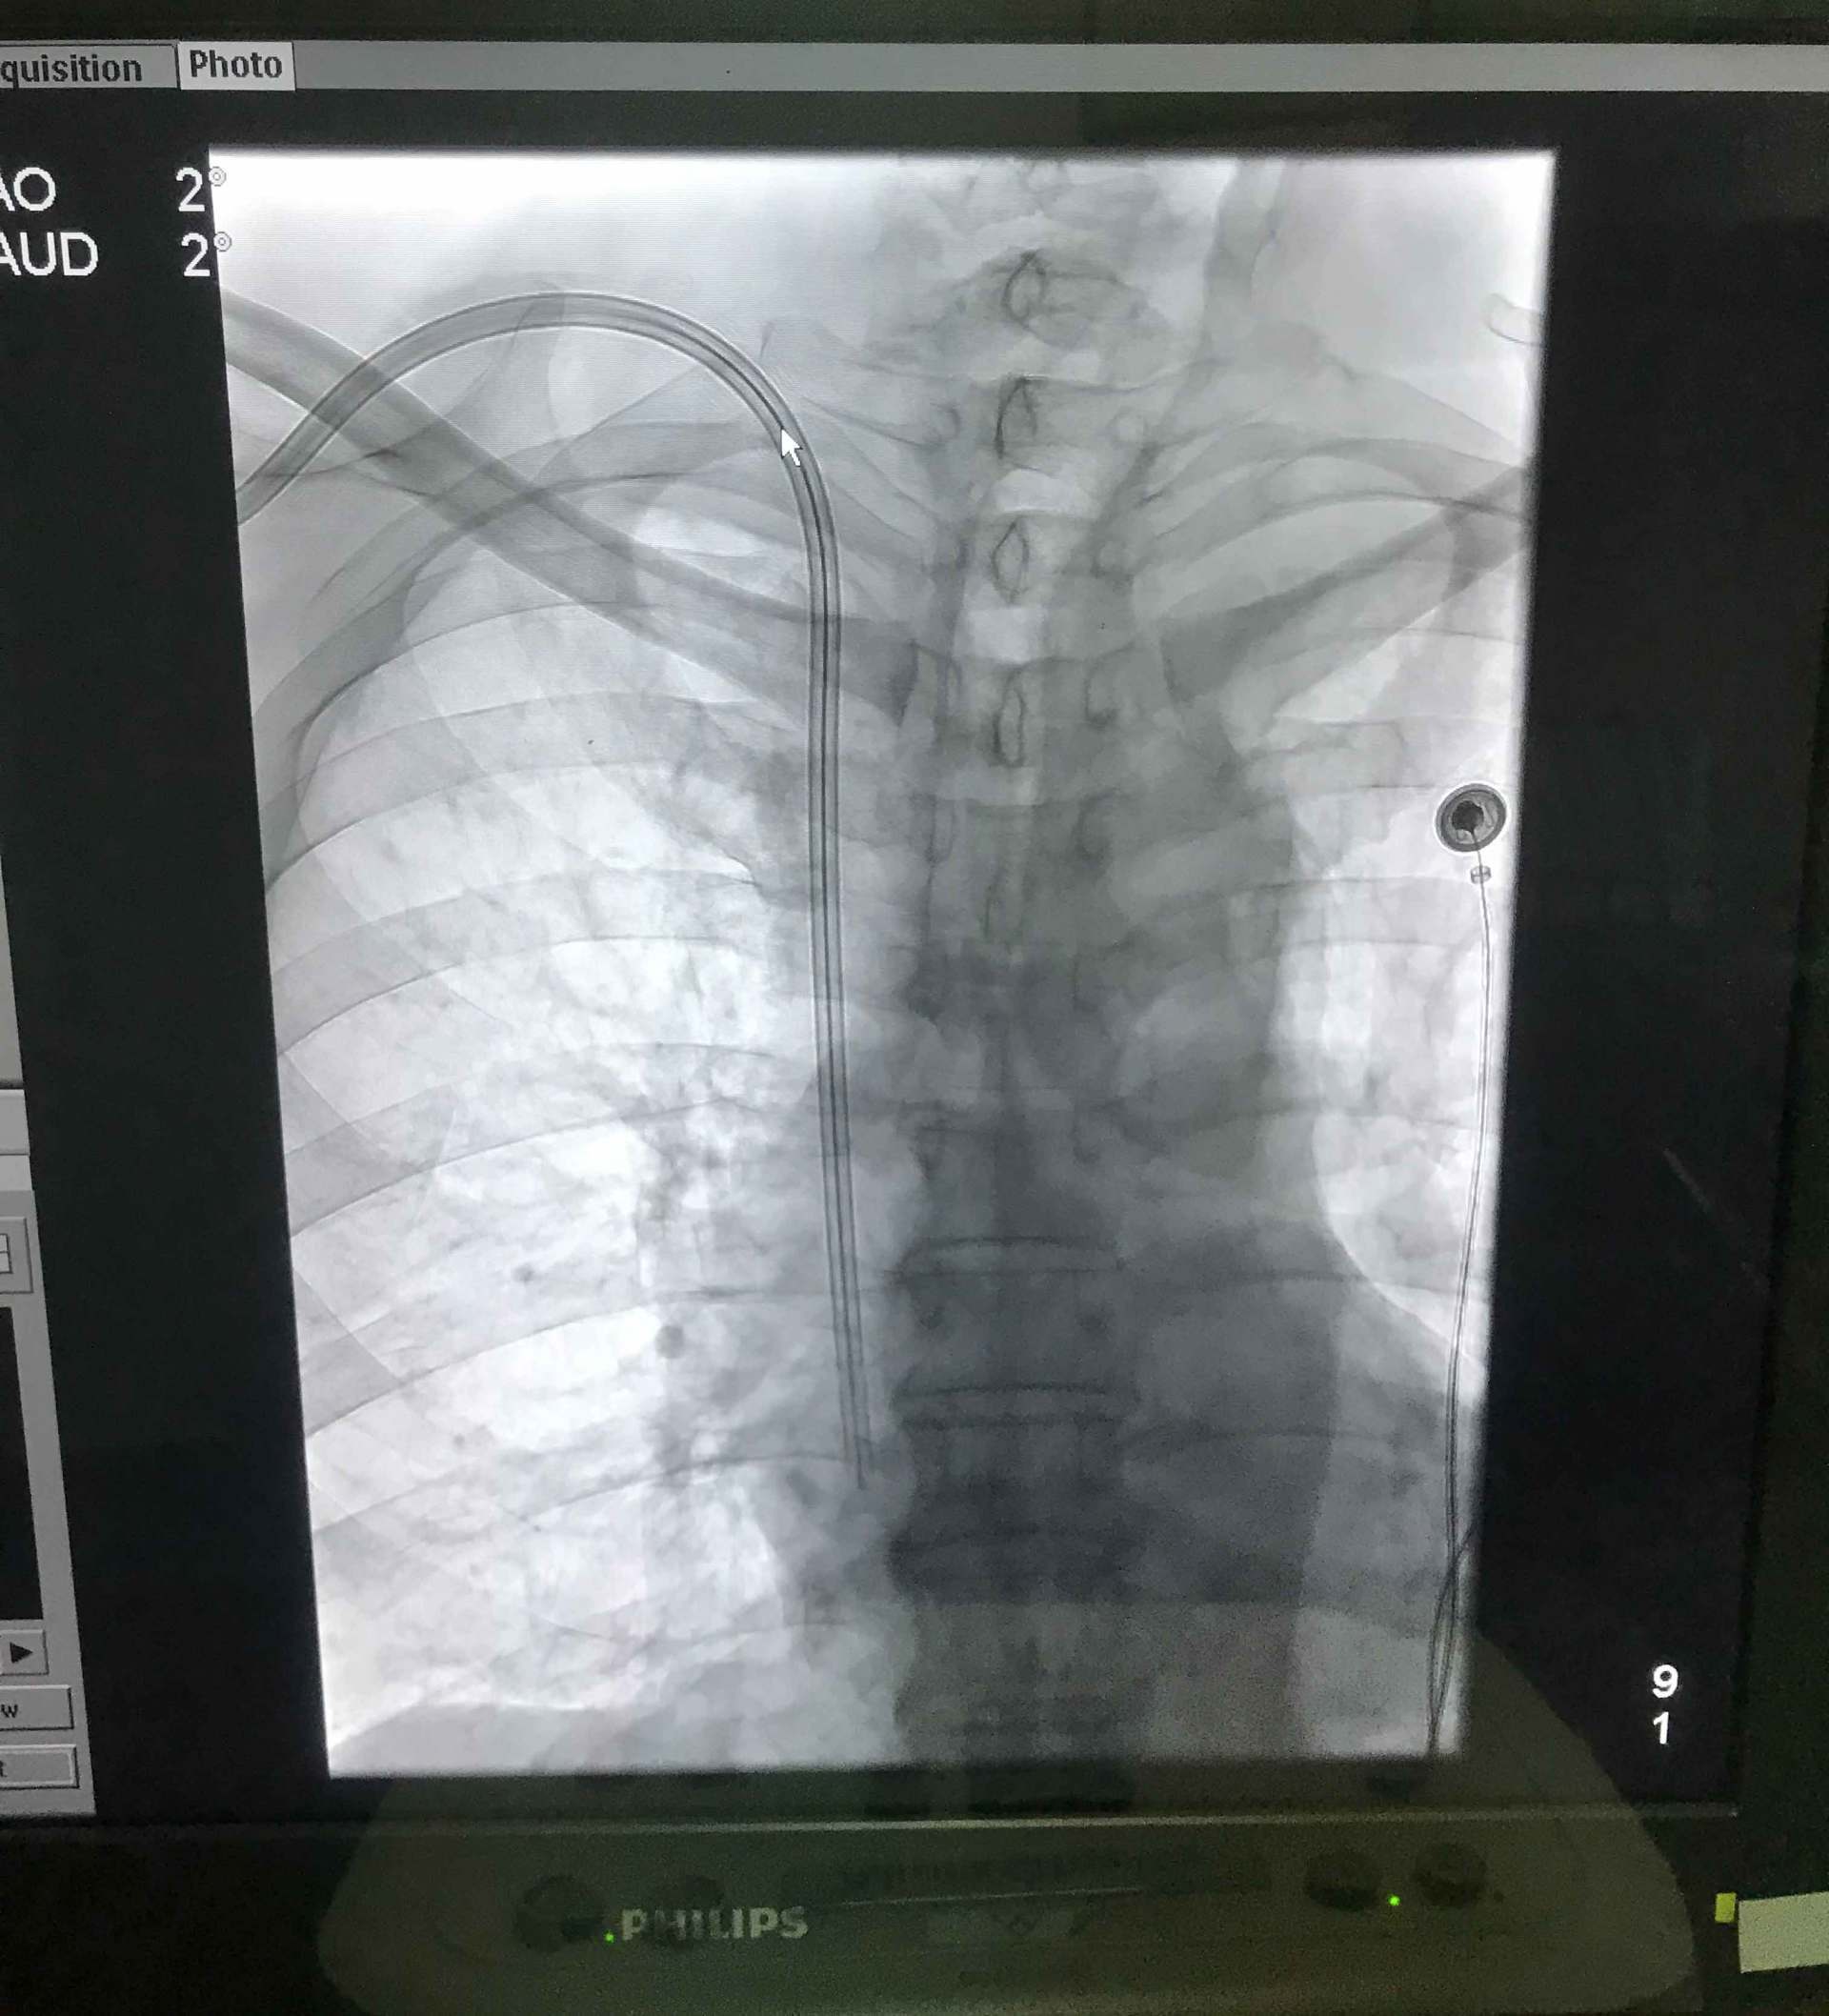

我科开展主要诊疗业务:急慢性肾炎、IgA肾病、急慢性肾功能衰竭、肾病综合征、糖尿病肾病、高血压肾病、多囊肾、系统性血管炎肾损害、蜂蛰伤及各种中毒类疾病。开展超声引导下肾活检穿刺术,开展自体动静脉内瘘成型术、自体动静脉内瘘血栓取出术、超声引导下动静脉内瘘球囊扩张成型术、DSA引导下动静脉内瘘球囊扩张成型术、DSA引导下带涤纶套皮下隧道式半永久导管置入术、带涤纶套皮下隧道式半永久导管拔出术。

DSA引导下带涤纶套皮下隧道式半永久管植入术